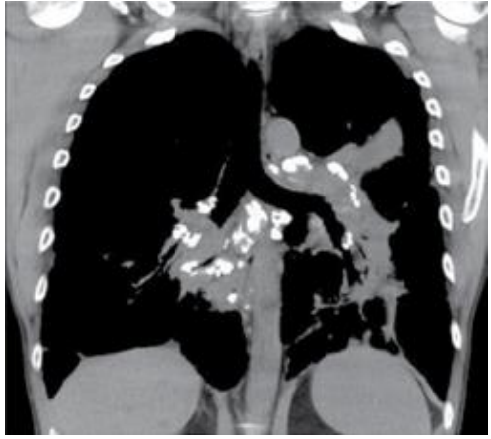

Paciente do sexo feminino, 46 anos, sem histórico de tabagismo, queixando-se de tosse seca e cansaço. A paciente realizou tomografia computadorizada como parte da rotina diagnóstica.

Em relação ao diagnóstico e às características radiológicas da sarcoidose, assinale a afirmativa correta.